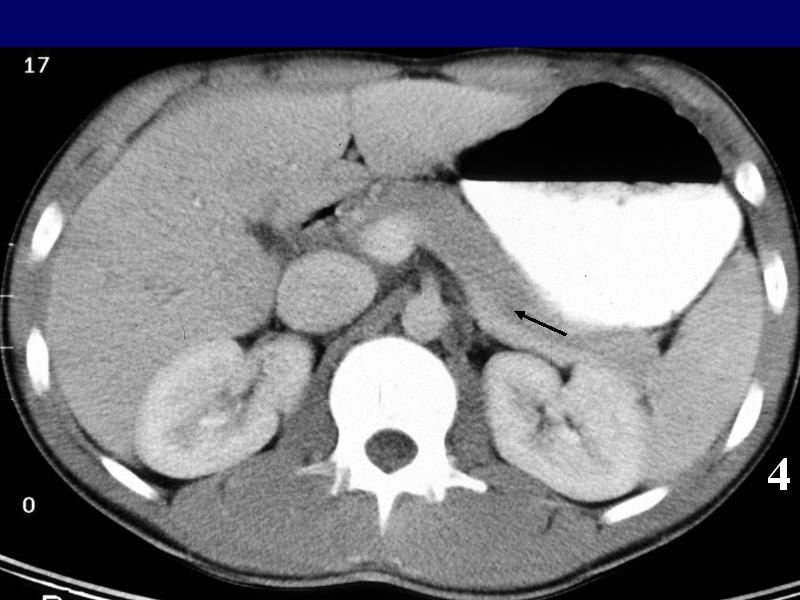

MS 190 CT 15